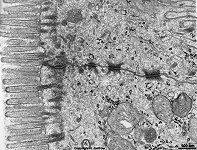

Miniaturbildübersicht Tight-junction (Zonula occuldens):

komplette Schlußleiste

mehrere Desmosomen (Ratte)

Tight-junctions (Barrienkontakte, Terminologia histologica: Junctiones occludentes; zumeist Zonulae occludentes; auch in Deutschen wird oft der englische Begriff tight-junctions selten occluding junctions verwendet) sind leistenförmige Kontaktstellen zwischen Zellmembranen, die elektronenmikroskopisch so eng erscheinen, als wären hier die Membranen miteinander verschmolzen.

Tight-junctions befinden sich stets in dem obersten, zum Lumen eines Hohlorgans oder Blutgefäßes hin gelegenen, also apikalen Bereich zwischen zwei benachbarten Epithel- bzw. Endothelzellen. Sie gehören zu den Schlußleisten, deren obersten Abschnitt sie darstellen und finden sich in einem etwa 100 bis 300 nm hohen, den gesamten Zellumfang umfassenden Bereich. Letzterer befindet sich oberhalb der Gürteldesmosomen (Zonulae adhaerentes) und Fleckdesmosomen, die die nach unten folgenden Abschnitte der Schlußleisten darstellen.